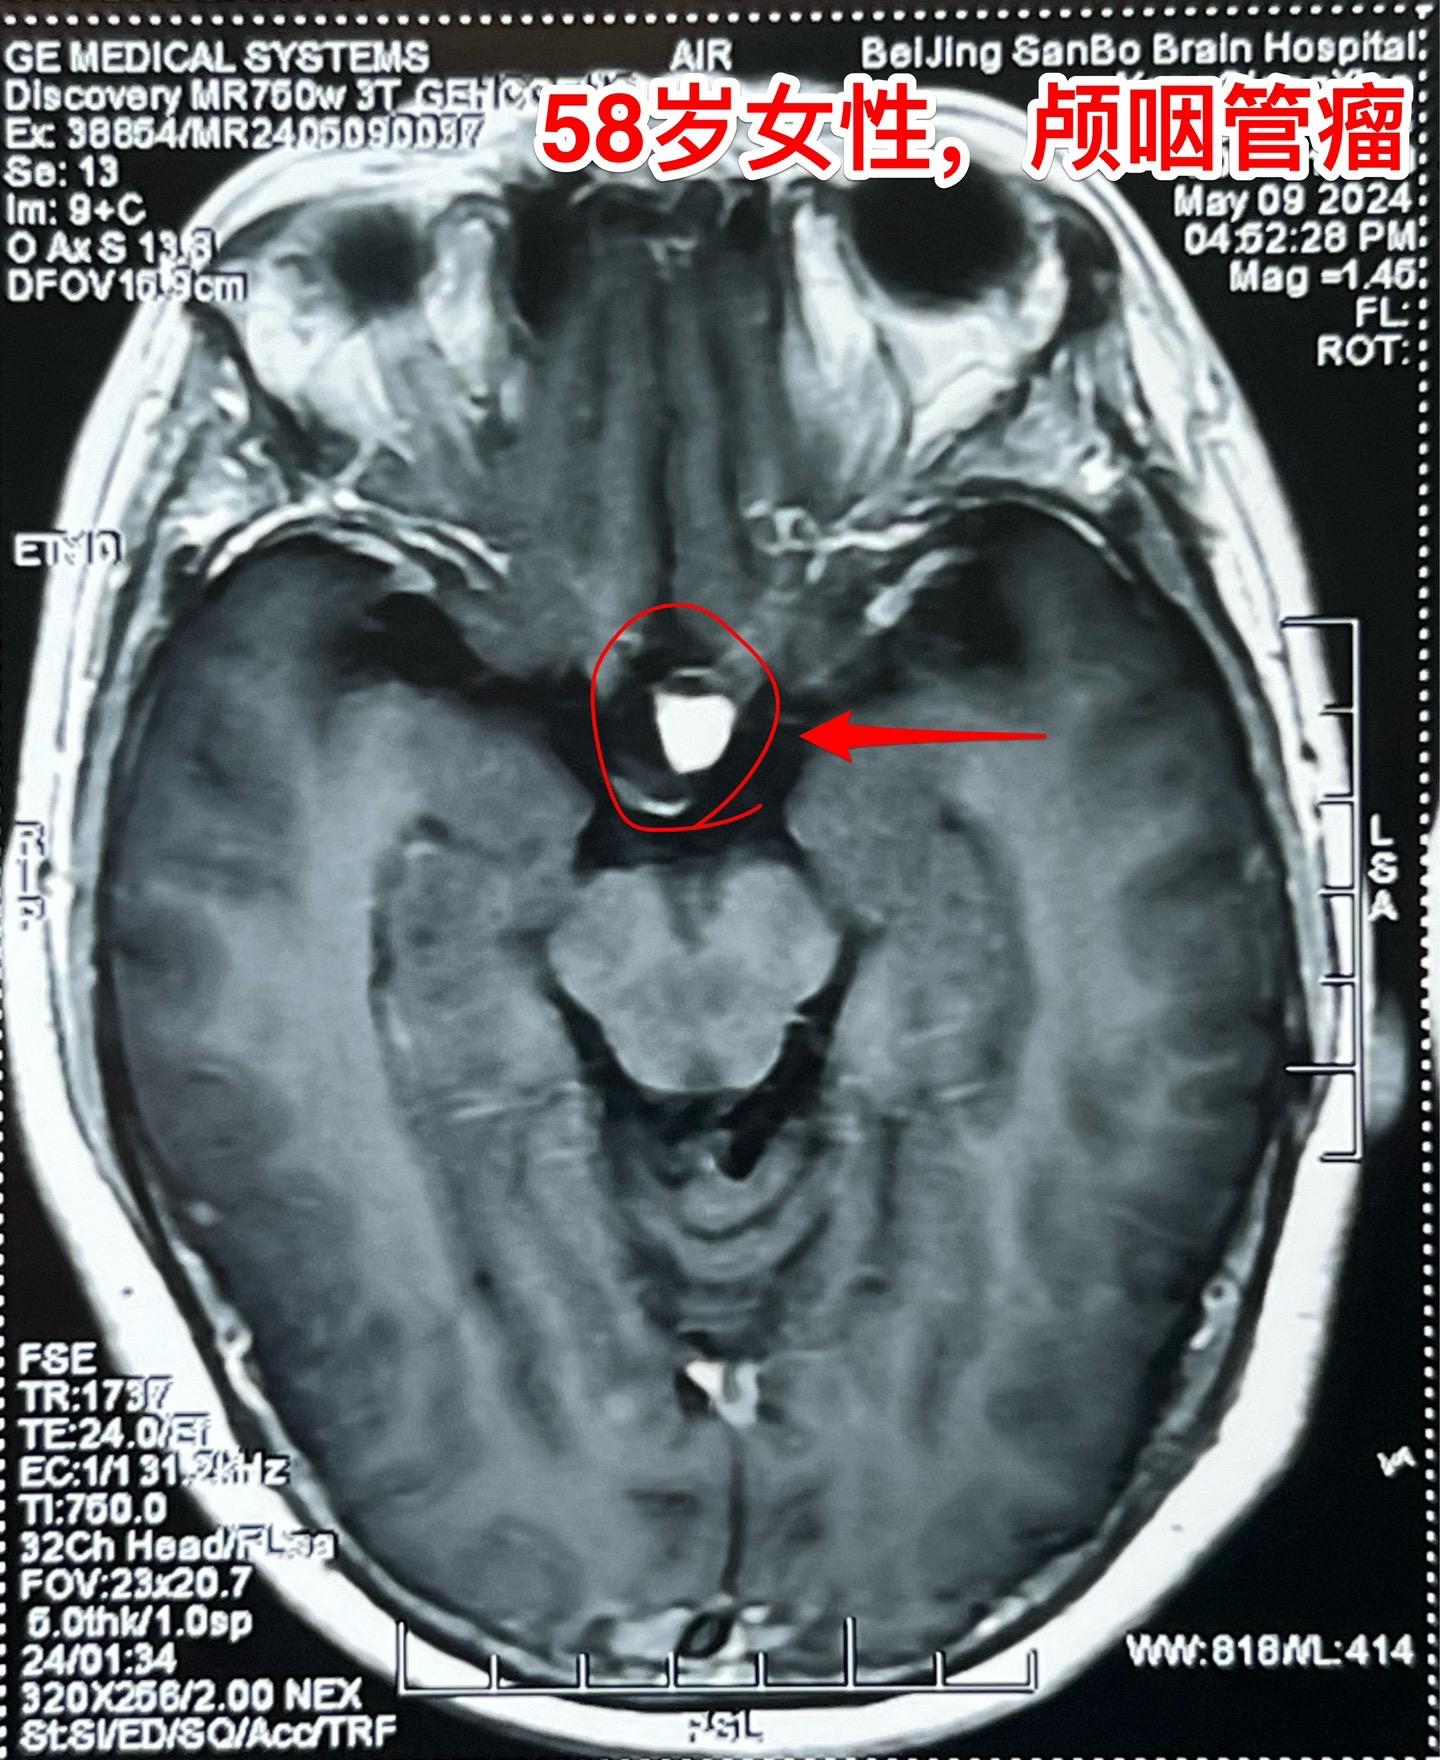

58岁女性视力下降。这是典型的颅咽管瘤。 这样的颅咽管瘤更适合翼点入路:瘤位于鞍上池内,直径约2厘米,乳头型颅咽管瘤。 病人的左眼视力更差,所以选择经左侧翼点入路。肿瘤得到完全切除。视力下降

58岁女性视力下降。这是典型的颅咽管瘤。 这样的颅咽管瘤更适合翼点入路:瘤位于鞍上池内,直径约2厘米,乳头型颅咽管瘤。 病人的左眼视力更差,所以选择经左侧翼点入路。肿瘤得到完全切除。颅咽管瘤视力下降